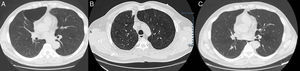

Presentamos el caso de un varón de 55 años de edad, exfumador desde hace 16 años de 50 paquetes/año, que acude a nuestro centro en junio de 2012 por presentar tos, expectoración diaria y disnea grado 1 de la MRC, sin exacerbaciones relevantes. Las pruebas de función pulmonar revelaron un patrón obstructivo en grado moderado, con una capacidad vital forzada (FVC) de 4.890cc (106%), un volumen espiratorio forzado en un segundo (FEV1) de 2.740cc (74%), una relación FEV1/FVC del 56% y una difusión de monóxido de carbono (DLCO) normal. La tomografía computarizada (TC) mostró un severo enfisema mixto de tipo centrolobulillar y paraseptal pulmonar bilateral, con afectación predominante de los lóbulos superiores, donde existían francas zonas de destrucción parenquimatosa pulmonar y una gran bulla de enfisema paraseptal a nivel del segmento anterior del lóbulo superior derecho (LSD) con un diámetro máximo de 9cm (fig. 1). Ante estos hallazgos y la persistencia de la sintomatología se propuso, al paciente, bullectomía quirúrgica que rechazó.

En noviembre de 2015 se realiza una TC de tórax de control donde se objetiva una imagen nodular de límites discretamente espiculados a nivel del LSD en situación paramediastínica en íntima relación con la grasa de la línea de reflexión pleural anterior, cuyas medias eran en el plano axial de 18×21mm de diámetro anteroposterior y transverso, y una longitud de 4cm medido en el plano sagital. Se seguían observando amplias zonas de destrucción pulmonar a nivel parenquimatoso en relación con el patrón de enfisema que predominaba a nivel de los lóbulos superiores y llamaba la atención la desaparición de la gran bulla a nivel del segmento anterior del LSD (fig. 1). Debido a la sospecha de un nódulo pulmonar solitario de naturaleza maligna se solicita una tomografía por emisión de positrones (PET) que mostró una lesión pulmonar moderadamente hipermetabólica en LSD compatible con malignidad, por lo que se decide extirpación quirúrgica de la lesión. Mediante cirugía torácica video asistida se realiza una resección en cuña, cuya anatomía patológica resultó ser un nódulo pulmonar esclerótico residual, compatible con hemangioma cavernoso trombosado y organizado con calcificación distrófica. En las pruebas funcionales respiratorias posteriores, la espirometría no mostró mejoría tras la desaparición de la bulla con una FVC de 4.600cc (100%), un FEV1 de 2.690cc (74%) y una relación FEV1/FVC del 58%.